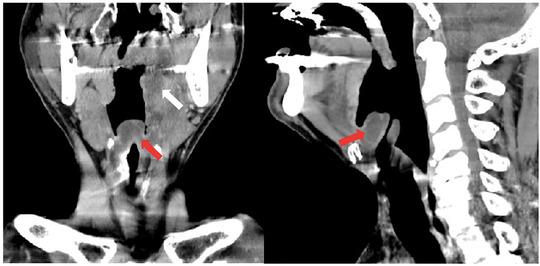

Male with sore throat and dyspnea.

https://cdn.ncbi.nlm.nih.gov/pmc/blobs/eadf/8898076/36e6a9b01b72/EMP2-3-e12686-g002.jpg

https://cdn.ncbi.nlm.nih.gov/pmc/blobs/eadf/8898076/3704a7e9c703/EMP2-3-e12686-g001.jpg